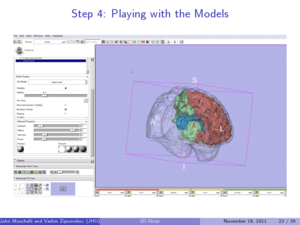

- 7.3 3D Slicer